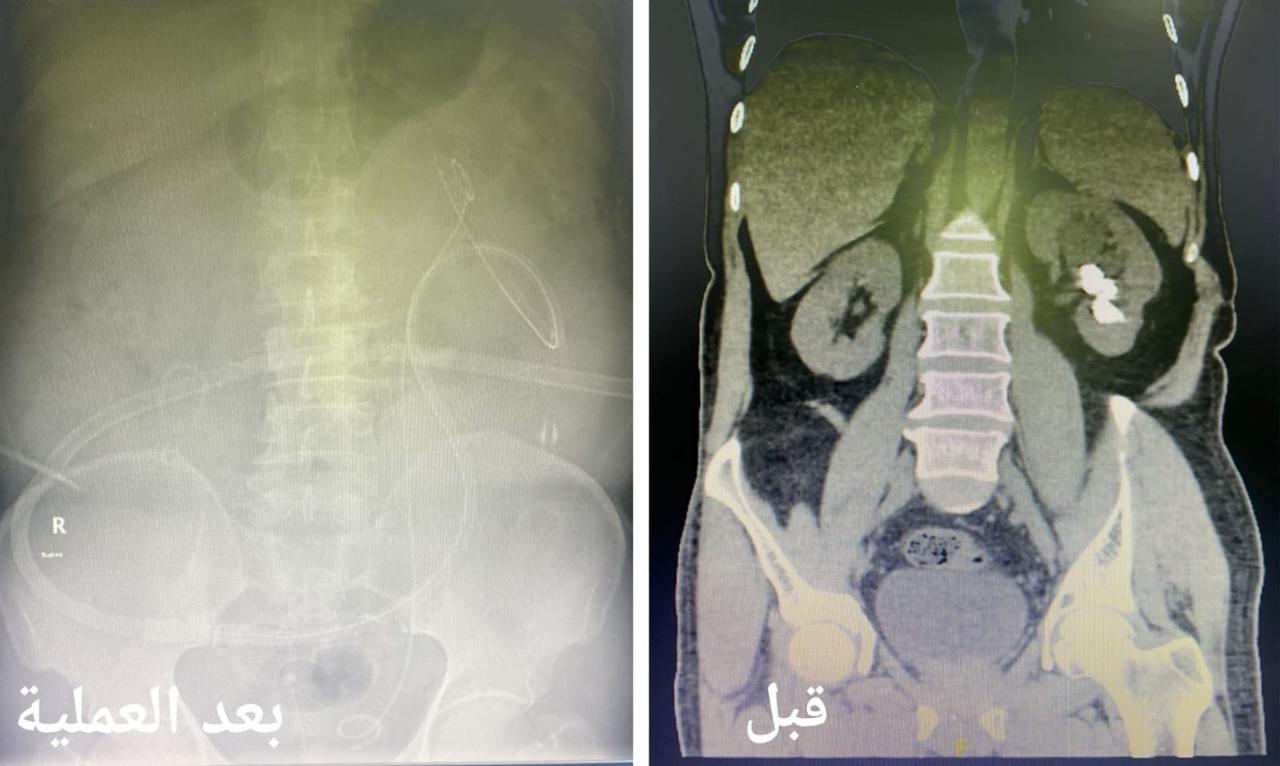

وأكدت أن الآم إزدادت خلال الأشهر الأخيرة مع المريض مع وجود تاريخ مرضي قديم يؤكد وجود حصوات في الجهاز البولي تسببت له تلك الاعراض مما استدعى سرعة إستكمال الفحوصات الطبية اللازمة والفحوص المخبرية للدم و البول و الفحوص الإشعاعية التصويرية بالأشعة المقطعية تبين خلالها وجود حصوات في حوض و تجويف الكلية اليسرى بحجم 3 سنتيمتر .

وأضحت أنه تم تجهيز المريض ونقله لغرفة العمليات وعمل تدخل جراحي كلوي دقيق بشق سنتيمتر واحد في الجلد بإستخدام التقنيات الطبية الحديثة لإستئصال الحصوات في جلسة جراحية واحدة و إزالتها بالكامل بواسطة ( المنظار الجلدي الكلوي ) و جهاز التيليسكوب و أدوات طبية صغيرة الحجم حيث تم إغلاق الشق الجراحي بخياطة واحدة دون حدوث أي مضاعفات ولله الحمد